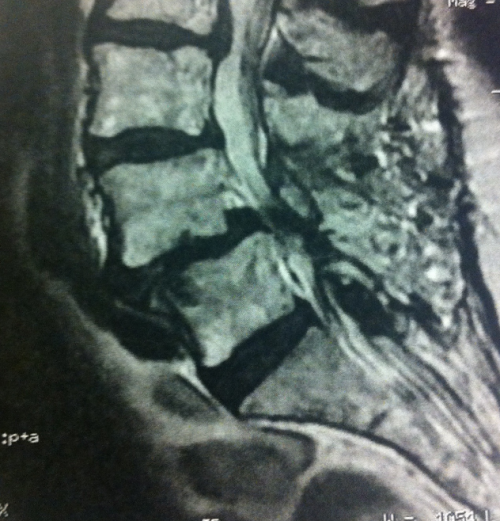

Bilan radiologique

Le bilan radiologique comprend des radiographies simples avec clichés dynamiques.

Il met en évidence la fracture isthmique et le glissement vertébral plus ou moins accentué lors des manœuvres de flexion et d’extension.

Le scanner précise les données radiologiques simples et l’ I.R.M. évalue l’intensité du rétrécissement latéral au niveau des trous de conjugaison venant comprimer les racines nerveuses. Ces examens évaluent également l’existence d’un canal lombaire étroit chez les patients plus âgés. L’I.R.M permet aussi l’étude des disques intervertébraux dans le cadre du bilan préopératoire, au niveau de la malformation, mais également au niveau des étages adjacents.